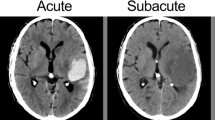

Moderation Effect of ICH Energy

Our findings indicate a significant positive moderation by ICH energy on the reduction of 30-day mortality following surgical treatment (OR: 0.932; 95% CI: 0.884–0.988; p = 0.01) (Table 2). To distinguish between patients with low and high nergye, we established the cut-off point for such moderation at 27.92 (p < 0.01). Examples of ICH with high and low energy are presented in Fig. 2. Among patients above this threshold (54.50%) surgical treatment was independently associated with a lower risk of 30-day mortality (OR: 0.113; 95% CI: 0.015–0.593; p = 0.02). Additionally, a lower GCS score upon admission (OR: 0.731; 95% CI: 0.632–0.83; p < 0.01), a larger volume of ICH (OR: 1.26; 95% CI: 1.021–1.53; p = 0.043), higher glucose levels at admission (OR: 1.246; 95% CI: 1.091–1.476; p < 0.01), and the presence of IVH (OR: 3.177; 95% CI: 1.366–7.769) were independently associated with an increased risk of 30-day mortality. Below determined threshold (45.50%) only older age (OR: 1.068; 95% CI: 1.025–1.120; p < 0.01) and the subtentorial location (OR: 1.020; 95% CI: 1.003–1.041; p = 0.031) were independently associated with higher risk of 30-day mortality (Table 3, Fig. 3).

We uncovered significant differences in the CT appearance of surgically treated ICH. Based on existing literature, ICH radiomics have not been analyzed for surgical treatment indications; however, it’s association with outcomes and the risk of ICH growth has been demonstrated [11,12,13]. This aligns with our findings that energy and entropy were independently linked to an increased risk of 30-day mortality in our study group. Another interesting finding in our study was the moderating influence of energy levels on 30-day morality postsurgical treatment. Patients with higher ICH energy levels may benefit more from surgical intervention, which likely stems from an increased risk of ICH expansion [16]. Consequently, early surgical intervention and the application of hemostatic materials could be crucial in prevention of further rebleeding. Interestingly, another study with comparable number of patients found that in both high and low energy groups, well-known outcome predictors like GCS score, glucose level, ICH volume, or presence of IVH [10] were significantly correlated with mortality only in patients exhibiting high ICH energy. This finding might indicate a divergent natural progression of the disease between these two patient groups. Therefore, further research into radiomics in ICH management could aid in clarifying the role of surgical treatment, including the identification of patient subgroups which might distinctly benefit from it.